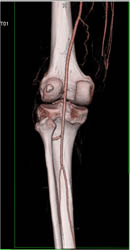

Diagnosis

Right Hepatic Artery Arises Off the Superior Mesenteric Artery (SMA) and Left Hepatic Artery Arises Off the Aorta